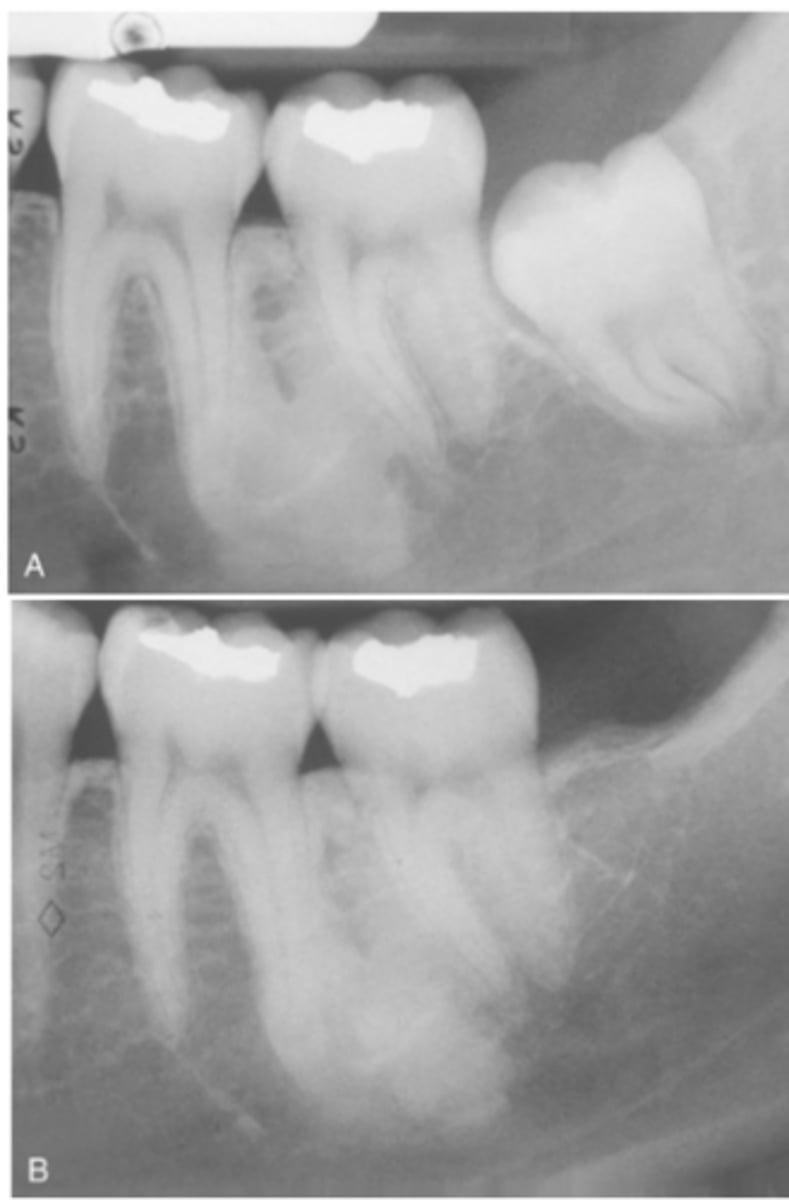

What do radiographic signs show in Idiopathic Osteosclerosis

Well-defined radiopacity

Most are associated to a root apex

If there is signs of cortical expansion in Idiopathic Osteosclerosis what needs to be taken?

biopsy

What is the treatment for Idiopathic Osteosclerosis

Follow-up with radiographs if discovered during adolescence